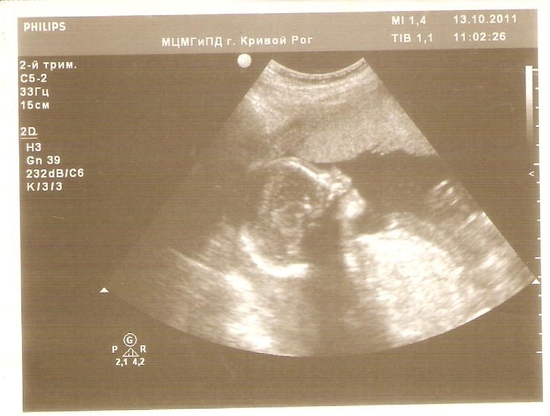

Плановое узи 21 неделя

Первый раз в жизни была на бесплатном государственном узи и поняла. что лучше буду платить деньги и будет на много удобней и комфортней. Записали меня на 9 утра. Пришла я без 5ти девять и оказалась 7й в очереди. Между женщин с номерками через одну прохожили люди иногородние, т.е я уже оказалась не 7я а где-то 14я. Дождалась я совей очереди, зашла в кабинет и услышала вопрос с упреком: а зачем вы делали узи на 17й неделе?? я: пол хотела узнать... в ответ послышалось недовольное бормотание, но я не расслышала что именно сказали. легла на кушетку, начался осмотр и тут малая начала выдавать))) узистка водит прибором по пузу а она в него ногой бах да бах, аж подпригивает рука врача))) и так весь сеанс. Ничего плохого не сказали насчет ребнка и меня. Малышка здорова, моя низкая плацентация уже оказывается высокая и никаких мутных околоплодных вод не обнаружено.Ребенка на мониторе не дали посмотреть В конце попросила сделать мне фото (естествено за деньги). И закрыв дверь кабинета решила: всё! только частные кабинеты узи!